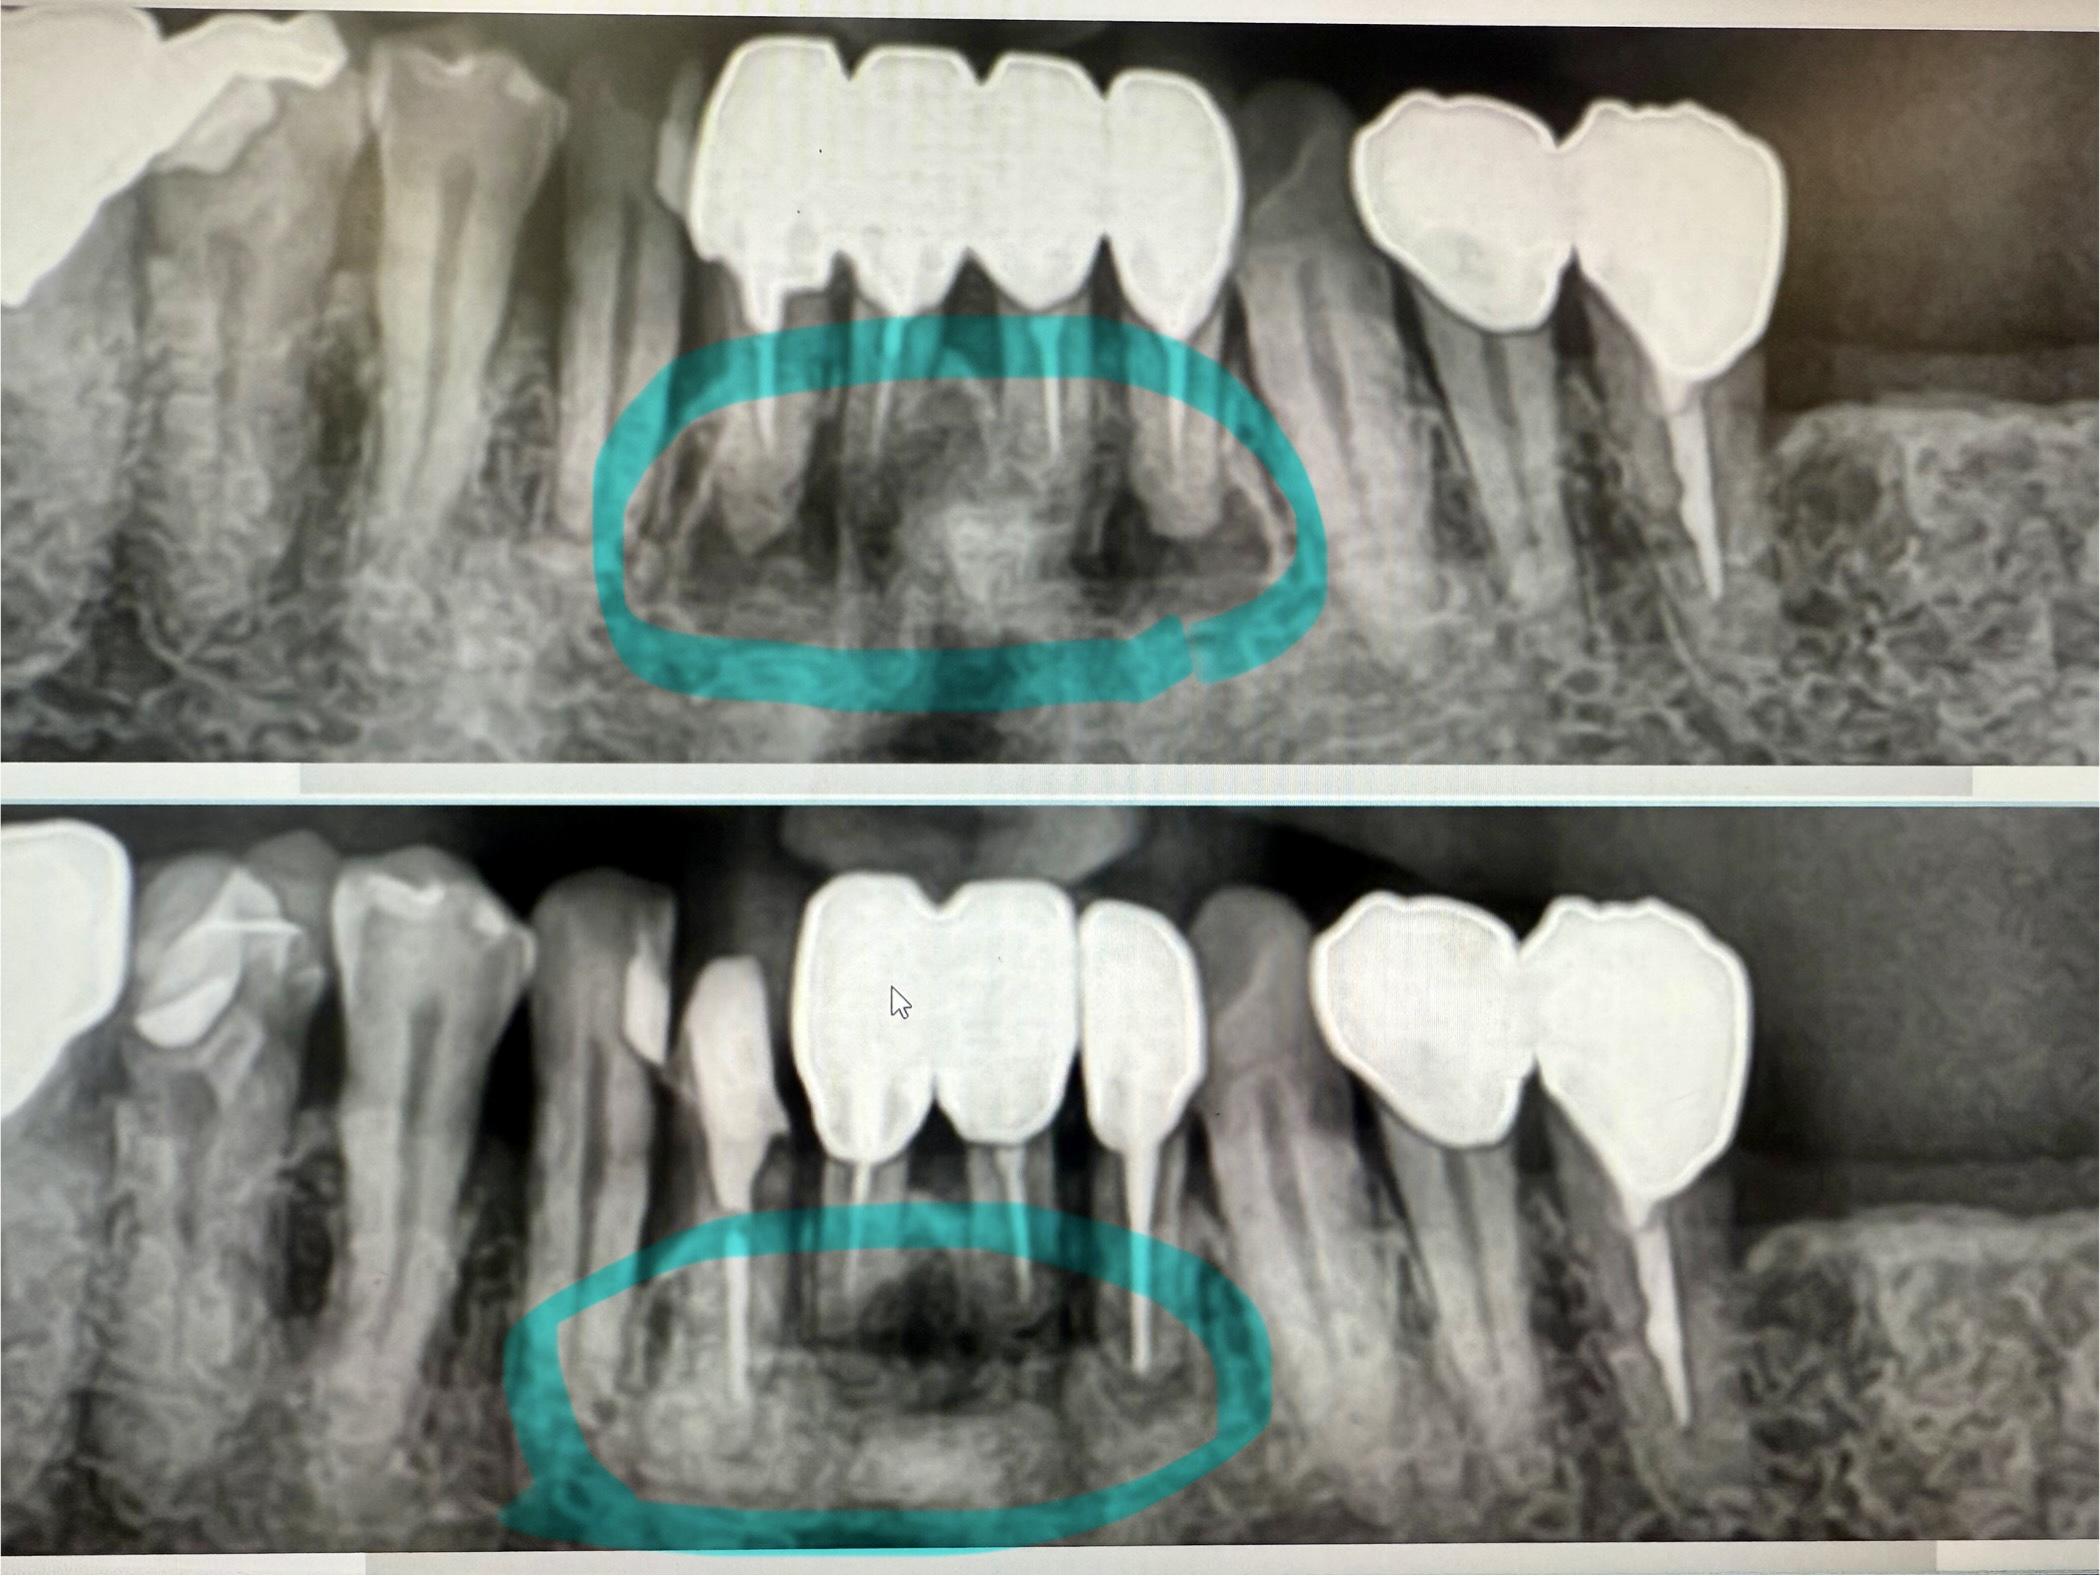

下の歯が上に上がってきている。上の歯が下に降りてきた。

それ、実はよくある現象です。結論からいうと「歯が伸びた」のではなく、噛み合う相手がいなくなって歯が動いてきた状態です。

この現象は歯科では挺出(ていしゅつ)と呼ばれます。

虫歯や、脱離で上の部分がなくなり、根っこだけが残っている場合も同様のことが言えます。

・噛み合わせがズレる

・食べ物が詰まりやすくなる

・歯周病・虫歯リスクが上がる

・将来的に治療が難しくなる(ブリッジ、インプラントや入れ歯などの設計が出来ない可能性)